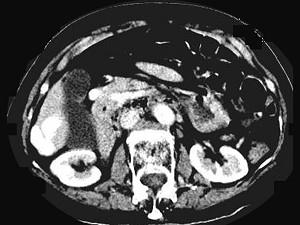

问题 女,70岁,发现乙型肝炎10年,3年前CT诊断为肝硬化,CT检查见图,最可能的诊断是 ( )

选项 A.肝癌 B.肝硬化、肝血管瘤 C.肝硬化、门脉瘤样扩张 D.肝门脉畸形 E.肝转移瘤、门脉扩张

答案 C